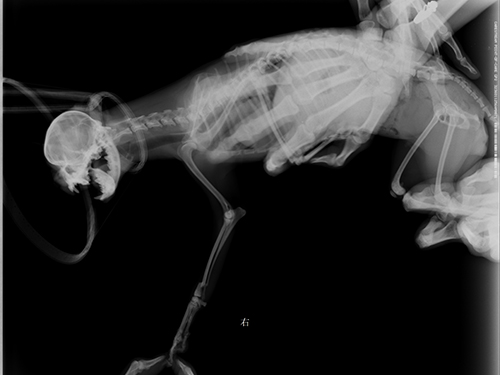

图3:术后正位片